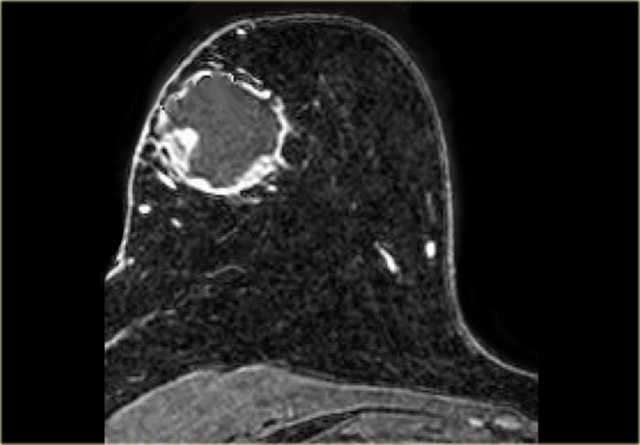

On the left an example of a metaplastic carcinoma with rim-enhancement.

This is not necessarily a typical presentation.

There is a small area of stromal fibrosis laterally in the left breast.